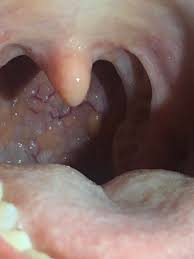

Tongue cancer is a type of cancer that starts in the cells of the tongue, and can cause lesions or tumors on your tongue. Many symptoms caused by oral tumors may be due to other, less serious conditions or other cancers. If you have oropharyngeal cancer, cancer cells form in the middle of the throat, including the tongue, tonsils, and pharynx walls. This isn't limited to my oral health, but i want to seek reassurance on some things that pester the back of my mind sometimes. Technically, there is no particular cause that leads to cancer of the mouth.

Not like oh yeah i stutter sometimes more the king's speech kind of stuttering. What you need to know about oral cancer Cancer is defined as the uncontrollable growth of cells that invade and cause damage to surrounding tissue. There are three types of biopsies, according to the american cancer society. In many cases, navigating a cancer diagnosis and understanding treatment plans can be. Signs and symptoms of cancer depend on where the cancer is, how big it is, and how much it affects nearby organs or tissues. Cancer that starts in the middle part of the throat is called oropharyngeal cancer. These cells can develop from oral hpv. Oral cancer often starts as a tiny, unnoticed white or red spot or sore anywhere in the mouth. Cancer that starts in the head and neck area can have many different names depending on. Oral cancer affects both men and women, especially those who are 40+. Cancer that starts in the mouth is called oral cavity cancer. What you should know about oral cancer.

An hpv infection of the throat can even lead to throat cancer, the same way hpv can lead to cervical cancer. For people who both smoke and drink heavily, the risk of oral cancer may be twice as high as the risk for people who do not. For this test, a small wand is moved around on your skin. If you experience any of the following jaw cancer symptoms. The more you know about your oral cancer, the more prepared you'll feel. Cancer that starts in the middle part of the throat is called oropharyngeal cancer. The tissue is checked for cancer cells. Ct scans can also be used to help do a biopsy and can show if the cancer has spread.

The tissue is checked for cancer cells. An hpv infection of the throat can even lead to throat cancer, the same way hpv can lead to cervical cancer. A sign, such as fever or bleeding, can be seen or measured by someone else. Always consider a second opinion. You may have heard other people say that their cancer was stage 1 or stage 2.. If you identify some of the signs and symptoms of mouth cancer described above, it is important that you make an appointment with your doctor or dentist as soon as possible in order to undergo testing and confirm the presence of cancer. If you experience any of the following jaw cancer symptoms. Sometimes the symptoms are barely noticeable in the early stages. that's a big reason why these cancers often go undiagnosed until the later stages, after they have spread to the lymph nodes. While the only chance to cure is surgery. This year, more than 51,000 u.s. Whether you're the giver or receiver of oral sex, you can contract and/or spread stis. If symptoms persist for several weeks or months, it is important to see your doctor so that, if oral cancer is present, it may be diagnosed as soon as possible. I'm quite prone to canker sores and while i know they're nothing to worry about since they heal on their own and none have persisted.